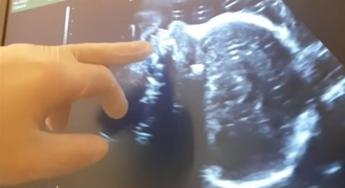

(Adnkronos) – "Il consumo di alcol in gravidanza è comune in molti Paesi e circa il 10% delle donne nella popolazione generale consuma alcol durante la gravidanza", secondo i "Rapporti Istisan 23/3" dell'Istituto superiore di sanità. Ma "non essendo stata a tutt'oggi stabilita una dose di alcol sicuramente esente da rischi durante la gravidanza", in occasione della Giornata mondiale della sindrome feto-alcolica e disturbi correlati (9 settembre), la Società italiana di neonatologia (Sin) ribadisce che "è opportuno astenersi completamente" dall'alcol "durante tutto il periodo" di gestazione. Alla vigilia della ricorrenza gli esperti lanciano un appello: sensibilizzare con una campagna ad hoc le future mamme sui rischi del consumo di bevande alcoliche in gravidanza. "Le donne – spiega la Sin in una nota – sono a più alto rischio di sviluppare un disturbo da uso di sostanze (Dus) durante il periodo fertile rispetto agli uomini, perché nel fenomeno della 'addiction' esiste una differenza di genere che le rende più suscettibili a passare dall'uso sporadico all'uso problematico e, infine, al disturbo da uso di sostanze conclamato". Ma in gravidanza "il consumo cronico di quantità eccessive di alcol può causare seri problemi a madre e neonato, aumentando il rischio di abortività spontanea, morte intrauterina, sindrome della morte improvvisa in culla, parto pretermine, basso peso alla nascita", elencano i neonatologi. "In particolar modo – aggiungono – può essere responsabile dell'insorgenza di difetti dello sviluppo fetale a carico di vari organi e apparati e di disabilità dello sviluppo neurocognitivo infantile. Queste disabilità, conseguenti all'esposizione all'etanolo in utero, sono note come disturbi dello spettro alcolico fetale (Fasd) e la Fas, o sindrome feto-alcolica, ne è la forma clinica più grave. Nell'ambito del complesso quadro della Fas – proseguono gli specialisti – le sostanze alcoliche possono causare inoltre la sindrome da astinenza neonatale (San), una condizione patologica causata dalla brusca cessazione dell'effetto di queste sostanze, cronicamente assunte dalla madre in gravidanza e trasferite al feto per via placentare". "Sebbene ci siano interventi efficaci per arginare e prevenire i rischi correlati all'alcol, in Europa molte donne in gravidanza continuano a bere e ci sono ancora poche azioni in atto a livello regionale e nazionale", rilevano i neonatologi italiani. "Dai Rapporti Istisan 23/3 – rimarcano – si evince infatti che l'Unione europea ha i tassi più alti al mondo di Fasd, oltre 2,5 volte la media globale". "Da anni, come Società italiana di neonatologia – dichiara il presidente Sin, Luigi Orfeo – insieme al ministero della Salute e all'Istituto superiore di sanità, auspichiamo ad aumentare la consapevolezza nelle donne in gravidanza, in età fertile e che stanno programmando una gravidanza, attraverso campagne di comunicazione e prevenzione. E' importante infatti garantire un'informazione quanto più corretta, immediata ed esauriente possibile, che renda le donne consapevoli, evitando di esporre loro ed i nascituri ai rischi di danni evitabili, sostenendo uno stile di vita più sano e azzerando il consumo di alcolici". —salutewebinfo@adnkronos.com (Web Info)